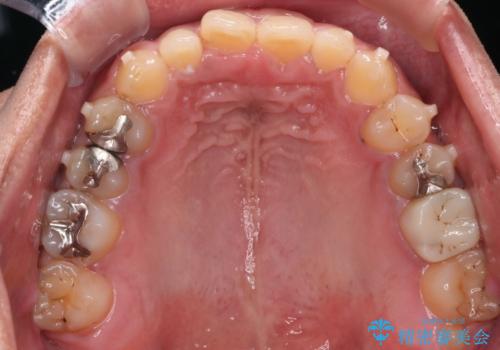

【モニター】インビザライン 前歯の捻れを治したい

- 30代男性

- 矯正装置

- インビザライン

- 治療計画

- 上下の前歯のがたつきを主訴に来院されました。インビザラインで治療可能と判断致しましたので、IPR(歯と歯の間を削る処置)と歯列弓拡大をして

がたつきをとる治療計画を立てました。

マウスピースをしっかり使用していただいたことで、主訴である前歯のがたつきも改善され

リファイメントも1回のみで治療を終了することが出来ました。